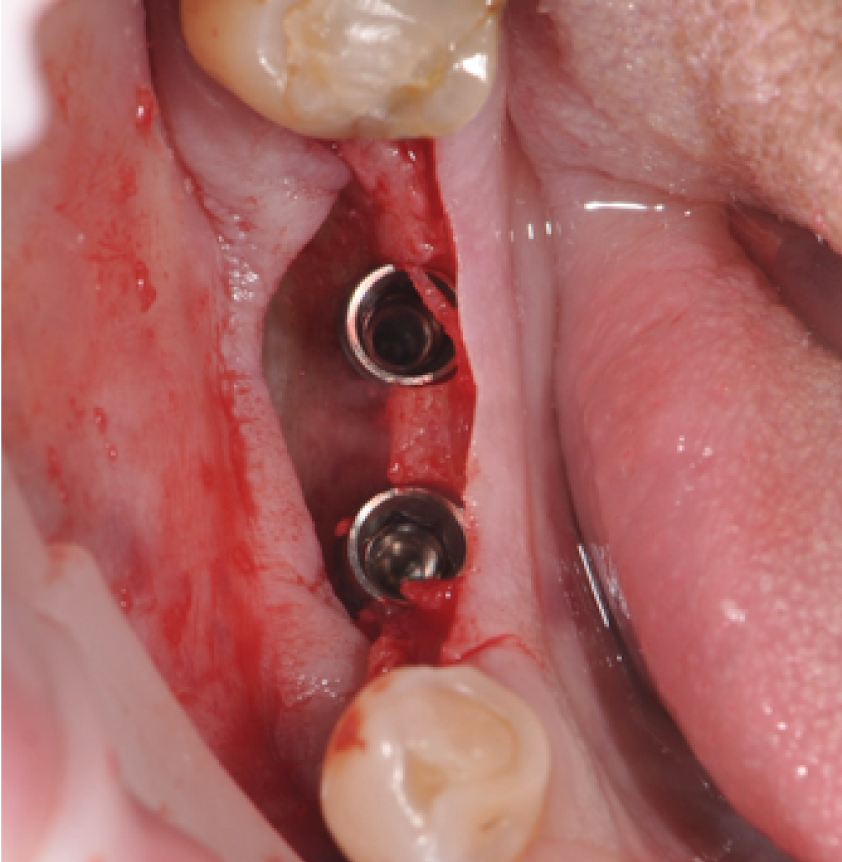

Director’s Clinical Cases

Director’s Clinical Cases

• Case presentations: Clinical pearl from real-world cases

• Case Presentations: Clinical Pearl and must-know takeaways